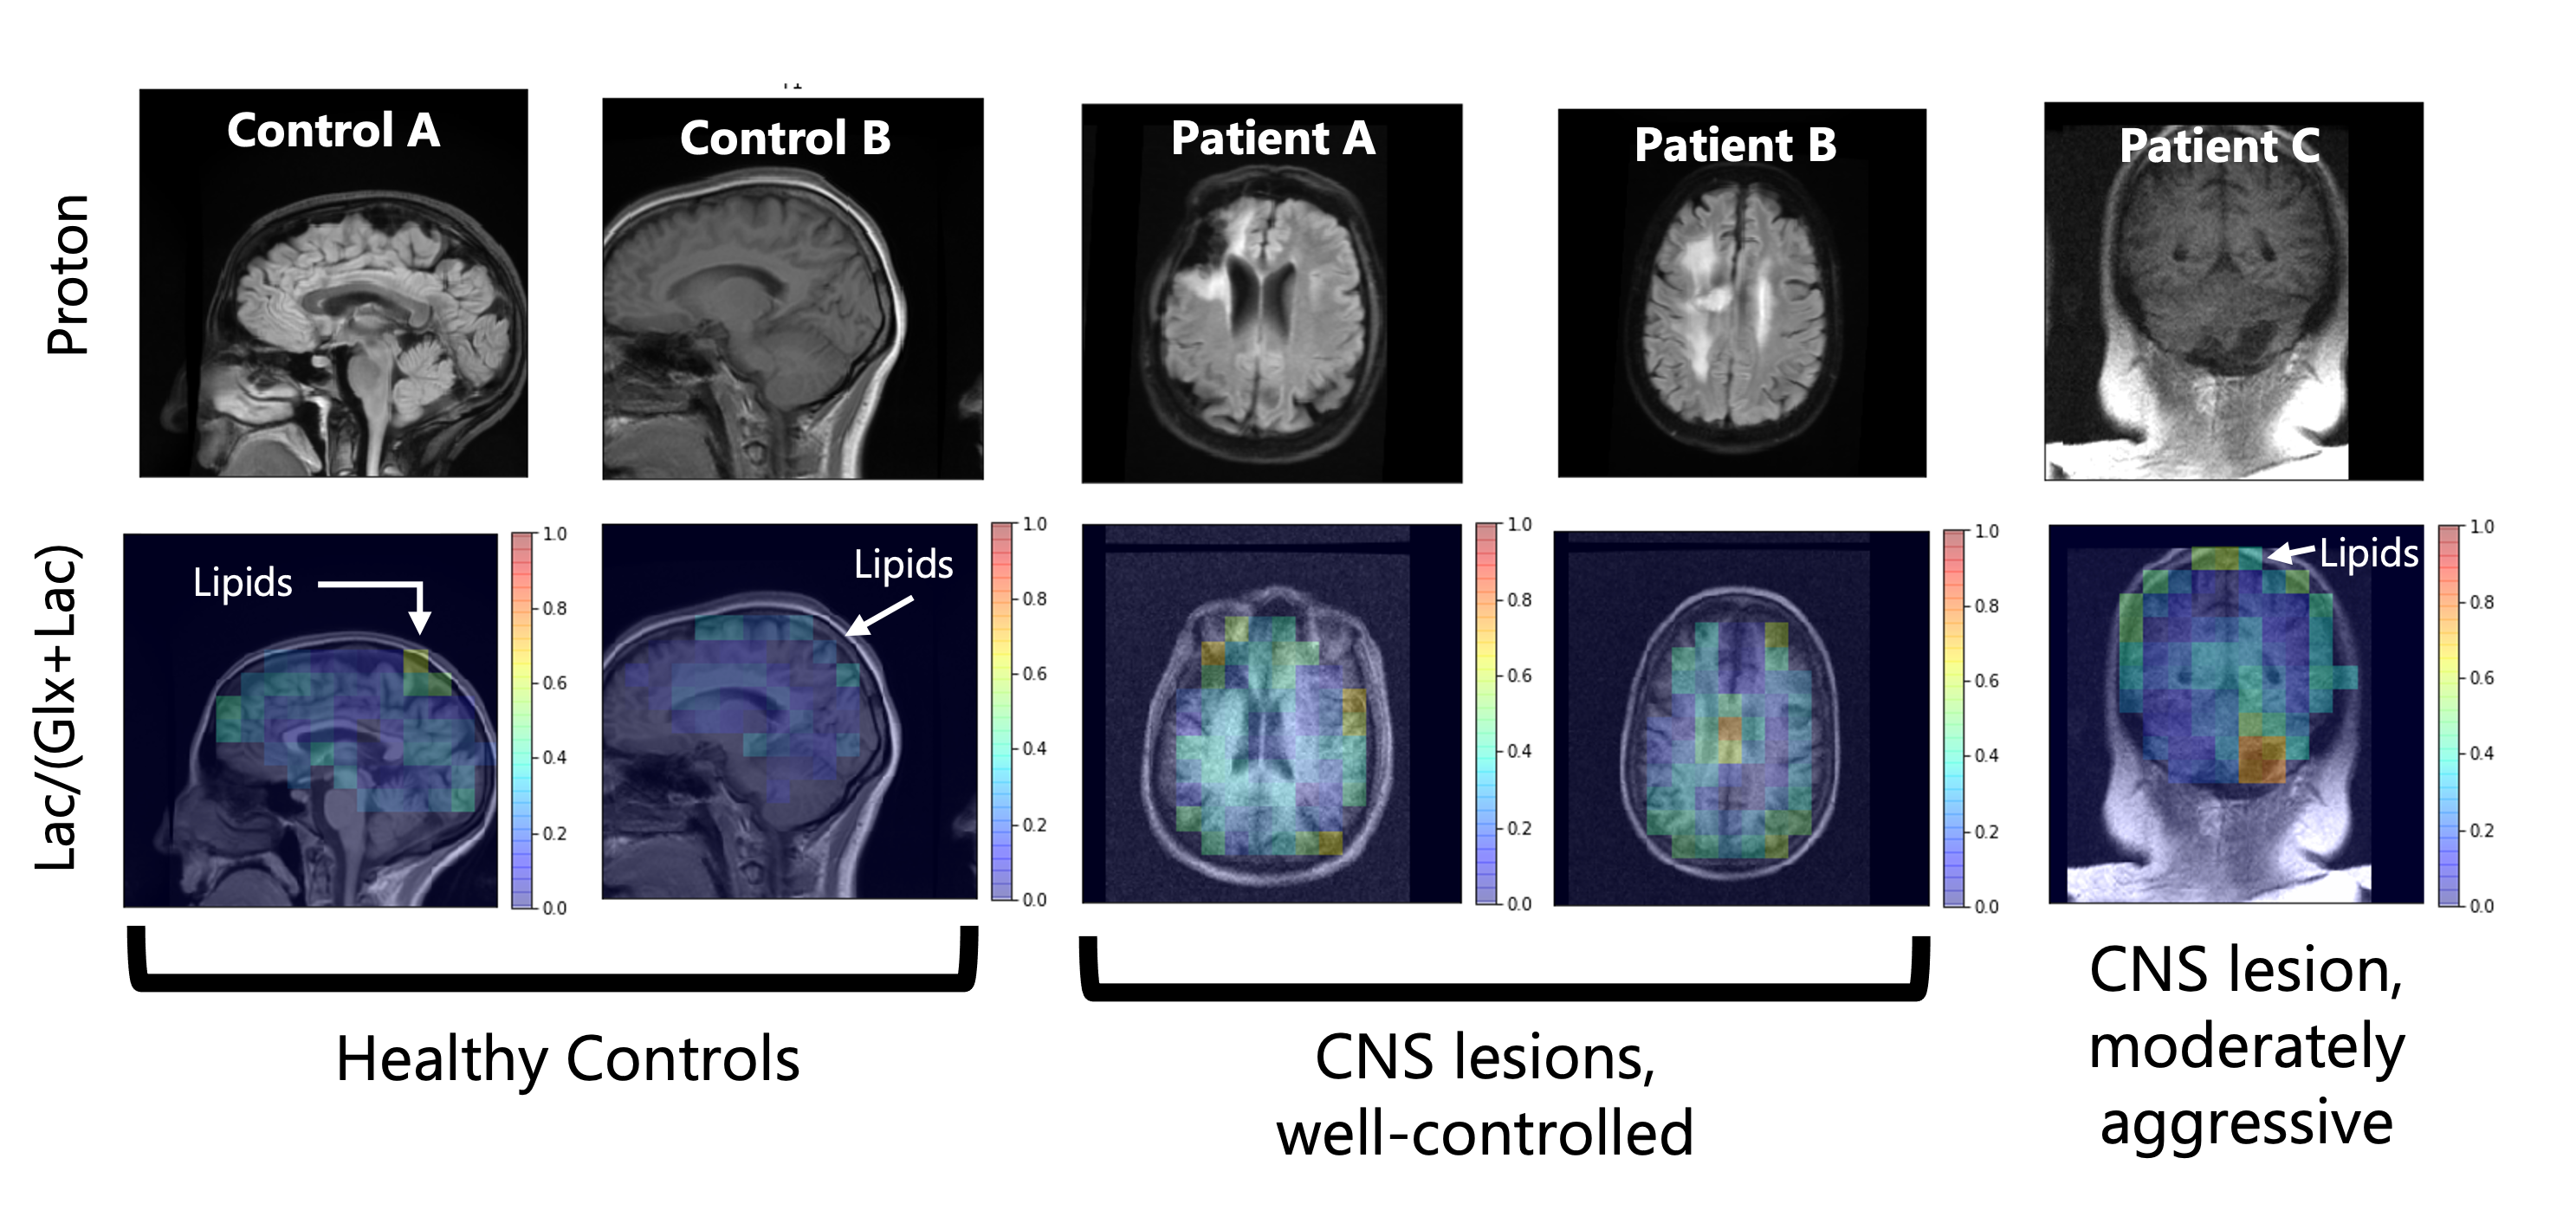

Representative anatomical scans and Lac/(Glx+Lac) maps from all five scan subjects – two healthy controls, two well-controlled CNS lesions, and a moderately aggressive CNS lesion. Healthy controls do not show elevated lactate, though natural-abundance signal from the lipids have overlapping resonances. The well-controlled CNS lesions (Patients A & B) have decreased Glx from necrotic regions of their lesions. The more aggressive lesion in Patient C has an elevated Lac/(Glx+Lac) signal around the lesion, potentially indicative of the Warburg effect.

Representative metabolic maps, corresponding anatomical scans, and example spectra of a healthy control, a patient with a well-controlled CNS lesion (Patient A), and a patient with a more aggressive CNS lesion (Patient C) are shown in Figures 1, 2 and 3 respectively. Figure 4 compares the Lac/(Glx+Lac) fraction across all five subjects. 3D whole-brain coverage is achieved in these DMI scans, including areas typically plagued by inhomogeneities in proton MRS such as near the brainstem. Good anatomical correspondence between the cerebrospinal fluid and lowered 2H-Glx is notable in the healthy control (Figure 1). Patient A shows a decrease in 2H-Glx in the necrotic region of the lesion without a corresponding increase in 2H-Lac (Figure 2). Patient C shows decreased Glx as well in the necrotic region of the lesion, with a moderate increase in Lac as seen most clearly on the Lac/(Glx+Lac) map (Figure 3). All patients show an elevated “Lac” signal near the skull due to partial voluming from the natural abundance 2H-lipid peaks overlapping the lactate resonance.